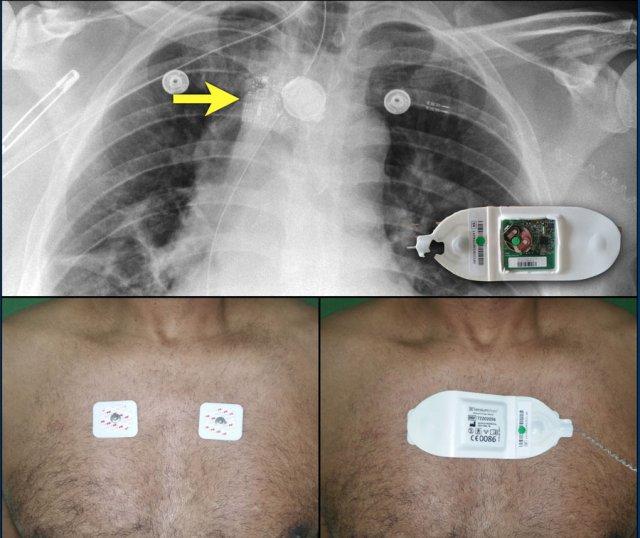

Máy ghi vòng lặp (Loop recorders)

Máy ghi vòng lặp là các thiết bị theo dõi tim có thể cấy ghép, dùng để ghi lại liên tục nhịp tim ở những bệnh nhân có triệu chứng hồi hộp đánh trống ngực hoặc ngất không rõ nguyên nhân.

Các thiết bị này được đặt dưới da.

Những thiết bị này ngày càng được thu nhỏ hơn và không nên nhầm lẫn với ổ đĩa USB.

Máy ghi vòng lặp có nhiều ứng dụng khác nhau, bao gồm theo dõi bệnh nhân có các cơn ngất không rõ nguyên nhân và đánh giá bệnh nhân mắc rung nhĩ, rối loạn nhịp thất hoặc rối loạn dẫn truyền.

Các máy ghi này có thể cung cấp khả năng theo dõi hơn một năm, có thể được kích hoạt bởi bệnh nhân hoặc tự động kích hoạt.

Một ví dụ khác về máy ghi vòng lặp.